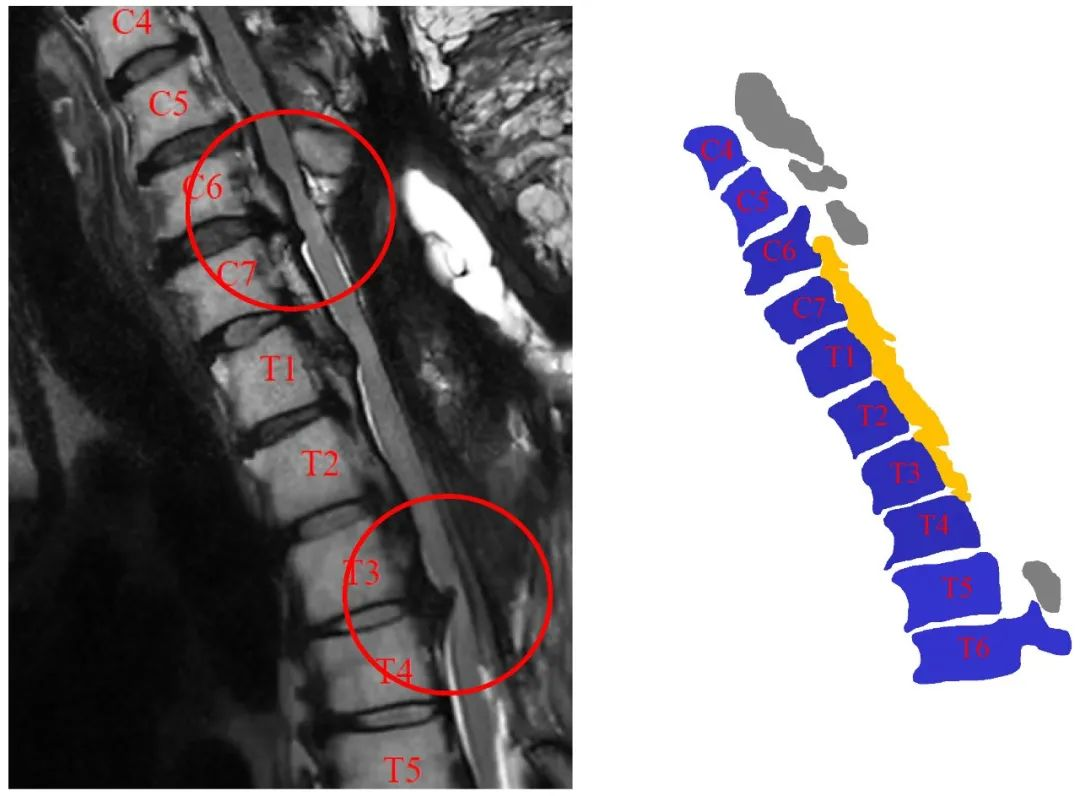

病史:M, 34 y/o

Numbness of right lower limb for 2 months, weakness for 1 week

Urination disorder

Body Weight: 120Kg; BMI: 39.5

影像资料:

Thoracic spinal stenosis(T2-T3)

Thoracic spinal stenosis decompression(T2-T3)

术后3个月: